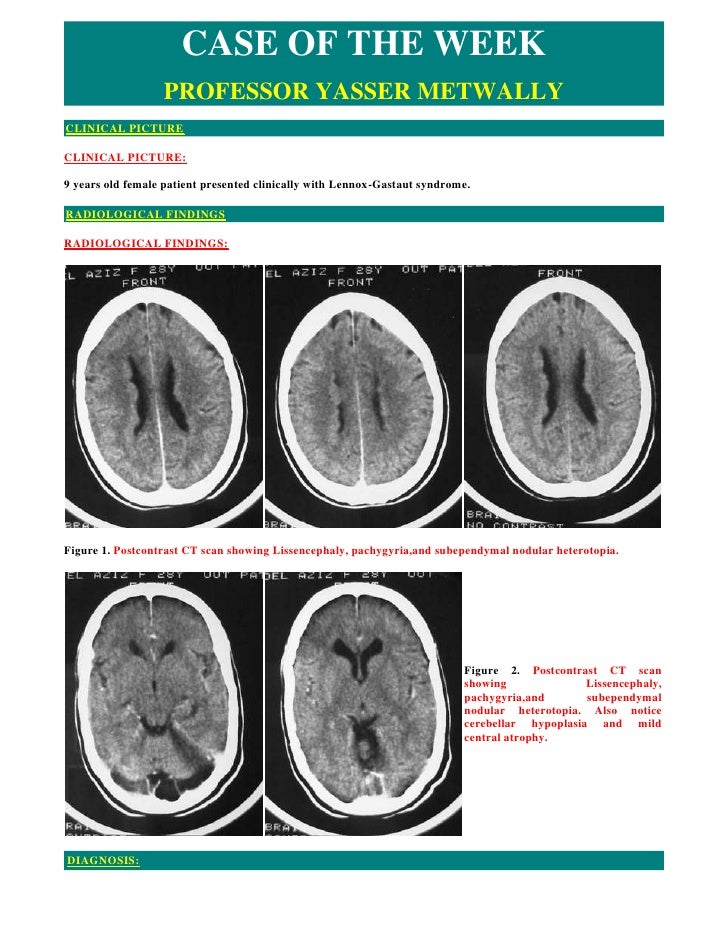

Case Record Cortical Dysplasia

Case Record Cortical Dysplasia from image.slidesharecdn.com

Jump to navigation jump to search. Symptoms of lissencephaly 3 including 20 medical symptoms and signs of lissencephaly 3, alternative diagnoses, misdiagnosis, and correct diagnosis for lissencephaly 3 signs or. Hypoplasia of pons & cerebellum. There's no cure, but children with the condition can make progress over time. Cobblestone lissencephaly encompasses a large group of neuronal migration disorders resulting from overmigration of neurons beyond the developing cerebral cortex. View lissencephaly research papers on academia.edu for free. Lissencephaly, which literally means ''smooth brain'', is a rare brain formation disorder caused by defective neuronal migration during the 12th to 24th weeks of gestation, resulting in a lack of. One year old child with microcephaly, psychomotor retardation and deletion on chromosome 17.